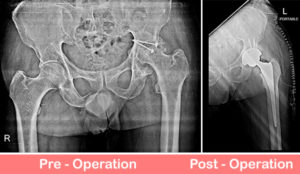

Total Hip Replacement – Dysplastic Hip

36 years old lady had developmental dysplasia of right hip. She had limp while walking since childhood and now had severe pain in walking. Her right leg was short by 3 cm.

We did Uncemented Total Hip Replacement in which we create new artificial joint restoring the normal hip biomechanics . ... Read more..